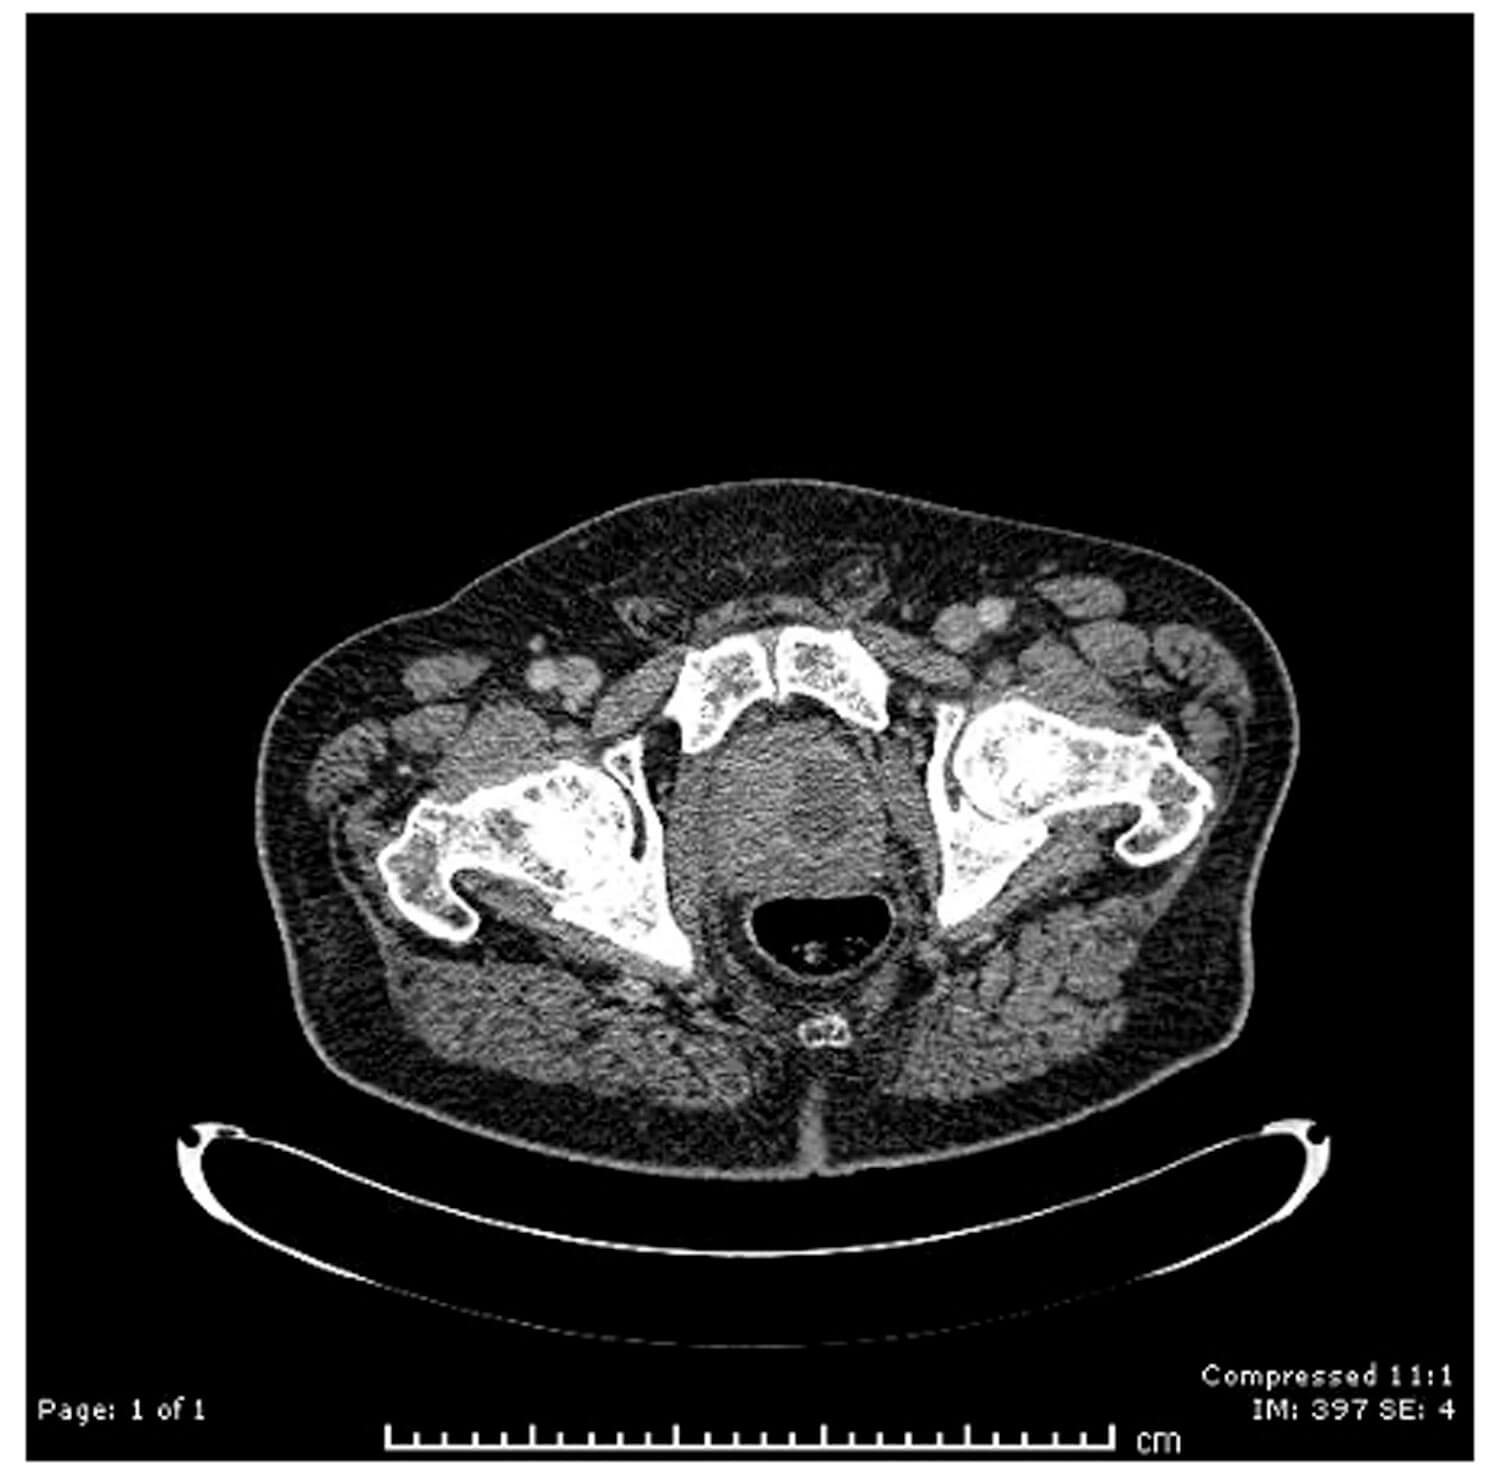

An 72-year-old male patient presented with fever and perineal pain of a few weeks’ duration. He was known to have LUTS and was on tamsulosin but was otherwise fit and well. Mid-stream urine sample showed no growth. Blood culture grew Citrobacter koseri, sensitive to IV Tazocin. However, the patient was not responding to IV antibiotics over 48 hours. CT of the abdomen and pelvis revealed a left prostate lobe abscess, localised to the transitional zone (Figure 1a and b). The patient was treated with transurethral deroofing under general anaesthetic (Figure 2) and was clinically well and discharged two days later on oral Augmentin® and trial without a catheter in 10 days. The patient was seen four weeks later in the outpatients department and was discharged having been judged to be making a good recovery.

Figure 1b: CT abdomen / pelvis (sagittal), left prostate abscess.